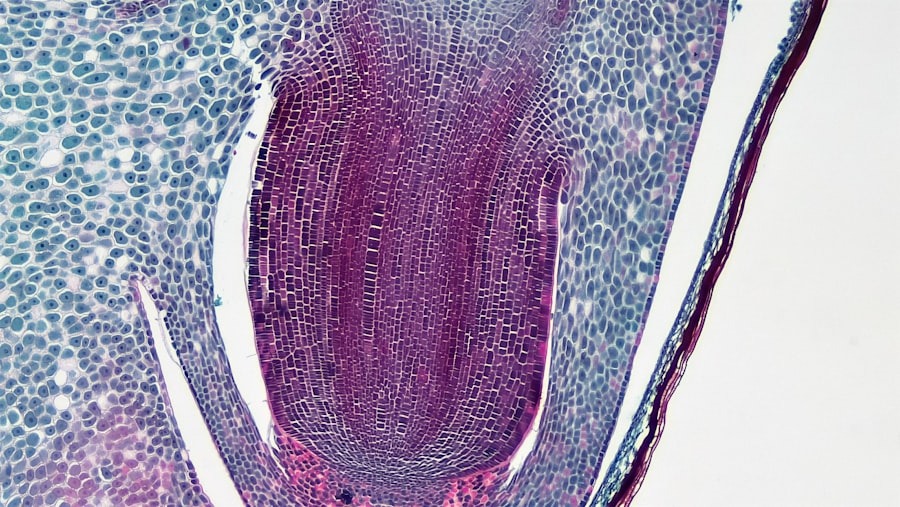

在顯微根管治療中,顯微鏡是最重要的設備之一。這種高倍放大鏡能夠讓牙醫清晰地觀察到根管的細微結構,包括根管的形狀、大小以及可能存在的裂縫或鈣化情況。透過顯微鏡,牙醫能夠更精確地進行清理和填充,從而提高治療的成功率。 除了顯微鏡,光學纖維也是顯微根管技術中不可或缺的一部分。光學纖維能夠提供良好的照明,使得牙醫在進行治療時能夠清楚地看到每一個細節。此外,這些設備通常設計得非常靈活,可以輕鬆地進入各種形狀和大小的根管,進一步提升了治療的效率和效果。 牙醫診所免費製作網頁+行銷年費優惠請參考牙醫診所免費製作網頁+行銷年費優惠。

顯微根管治療的流程通常包括幾個關鍵步驟。首先,牙醫會對患者進行詳細的檢查,包括X光檢查,以確定根管的具體情況。接下來,牙醫會使用局部麻醉來減輕患者的不適感,然後開始進行根管的清理和消毒。在這一過程中,顯微鏡的使用使得牙醫能夠精確地定位感染區域,並徹底清除病變組織。 在清理完成後,牙醫會進行根管的填充。這一步驟同樣需要高精度,以確保填充材料能夠完全密封根管,防止未來再次感染。最後,牙醫會對治療區域進行檢查,並根據需要安排後續的修復治療,如牙冠或其他修復體的安裝。整個過程中,顯微根管技術不僅提高了治療的精確性,也大大減少了患者的不適感。